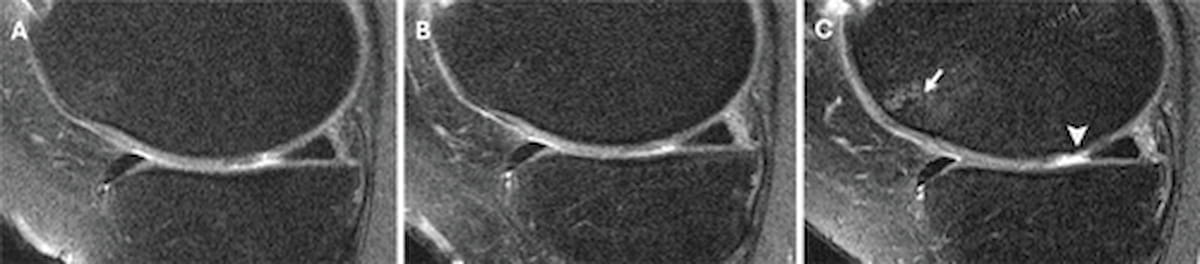

New MRI Study Questions Use of Corticosteroid Injections for Knee OA

While corticosteroid injections reportedly facilitate short-term pain relief for those with knee osteoarthritis (OA), emerging magnetic resonance imaging (MRI) research suggests that hyaluronic acid injections may provide more sustained long-term …